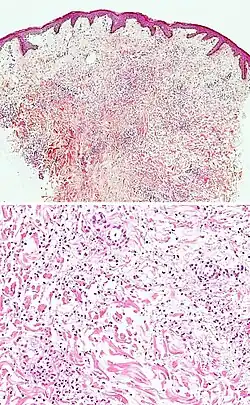

| Pigmented purpuric dermatosis |

|

| Kaposi’s sarcoma in patch stage | The patch stage typically shows irregular proliferation of jagged vascular channels in the dermis below an integral epidermis. The so-called promontory sign is sometimes found in patch stage lesions and denotes vascular spaces surrounding pre-existing blood (see image).[23]

vessels |